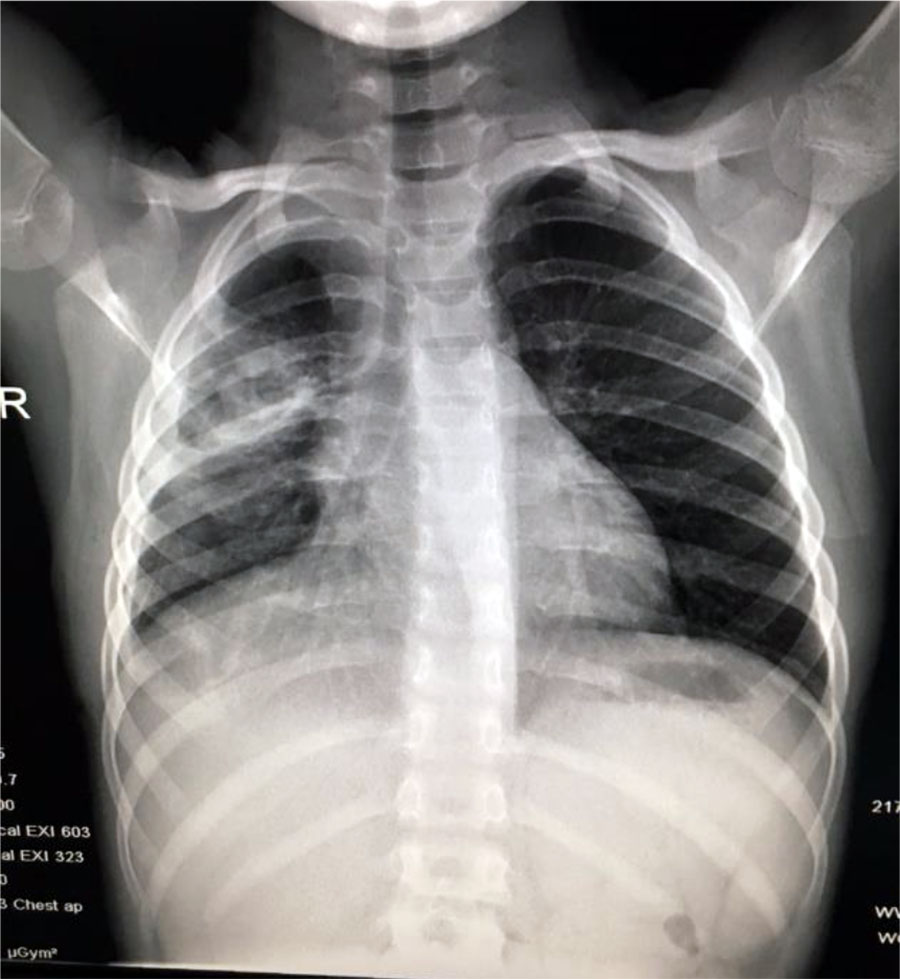

Blood test showed an increased number of leukocytes (37170/mmc) with predominance of neutrophils (92%) and an important inflammatory syndrome (CRP=252mg/l). Chest x-ray at the onset showed an opacity located on the upper right pulmonary lobe and presence of fluid in the right costo-diafragmatic sinus (Fig.4).

Fig. 4. Opacity located on the upper right pulmonary lobe and presence of fluid in the right costo-diafragmatic sinus